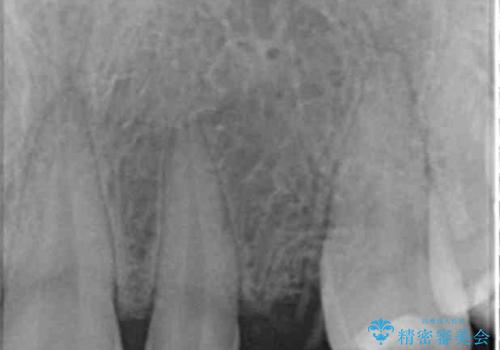

骨造成を伴う 前歯部インプラント治療

- 欠損している前歯のインプラント治療を希望され来院されました。

適切なインプラント埋入を行い、不足している骨量を補うため骨の造成を併用したインプラント治療を計画します。

前歯のインプラント治療は骨量・歯肉の厚み・インプラントの方向をしっかりと計画することで、審美的で長持ちを期待できるような仕上がりとなります。